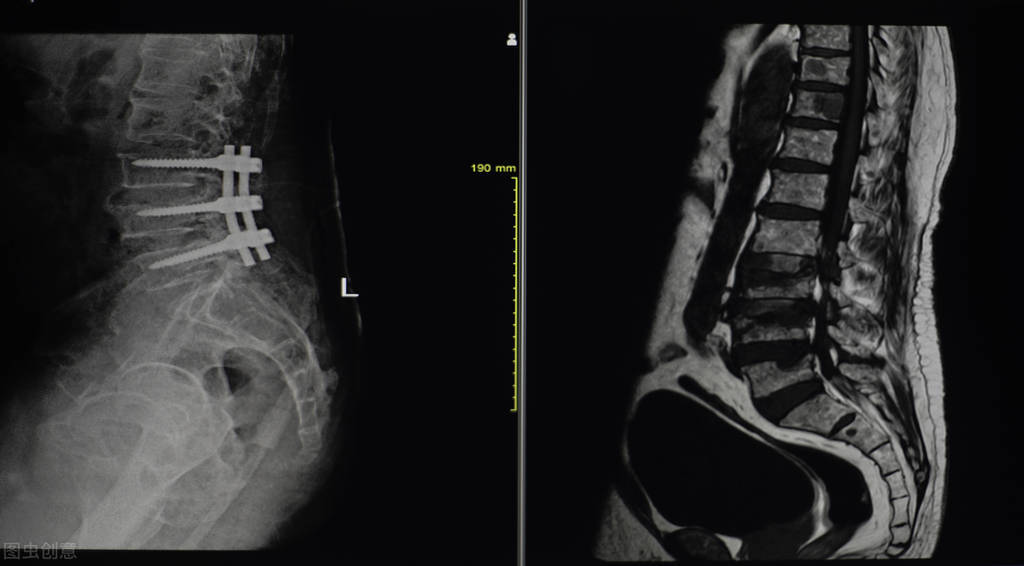

没错,一拍片子, 腰4、5椎体压缩性骨折 。骨科看了,治疗并无特殊,佩戴支具即可,于是,定制支具。